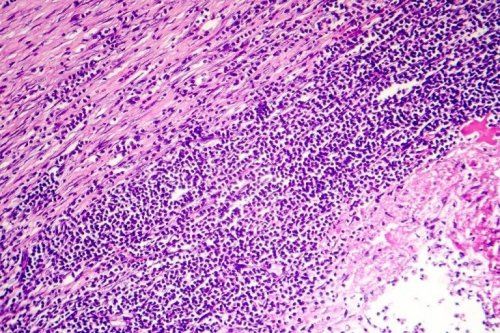

La pericardite è un’infiammazione del pericardio, la membrana a forma di sacco che circonda il cuore. Questa membrana è composta da due strati e, fra questi, è contenuto un piccolo volume di un liquido che serve da lubrificante e permette ai due strati di slittare l’uno sull’altro, senza provocare frizioni.